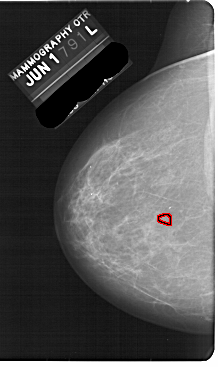

A_1870_1.LEFT_MLO

LEFT_MLO LINES 5491 PIXELS_PER_LINE 3331 BITS_PER_PIXEL 12 RESOLUTION 43.5 OVERLAY

FILE: A_1870_1.LEFT_MLO.OVERLAY

TOTAL_ABNORMALITIES 1

ABNORMALITY 1

LESION_TYPE CALCIFICATION TYPE PLEOMORPHIC DISTRIBUTION CLUSTERED

ASSESSMENT 4

SUBTLETY 1

PATHOLOGY BENIGN

TOTAL_OUTLINES 1

BOUNDARY